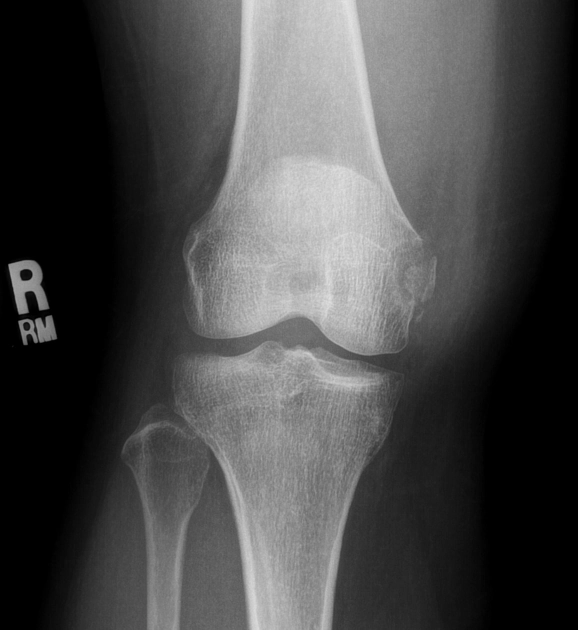

• Gãy bong khớp gối

Gãy Segond (Gãy bong mâm chày do đứt ACL)